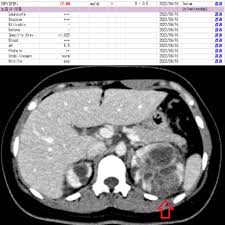

4. 방광염과 왼쪽 아랫배 통증

방광염은 여성에서 왼쪽 아랫배 통증을 유발할 수 있는 흔한 원인 중 하나입니다. 여성은 구조적으로 요도가 짧아 세균 감염이 쉽게 일어나며, 초기에는 소변을 자주 보거나 아랫배가 묵직하게 당기는 증상이 나타날 수 있습니다. 방치하면 방광염은 신우신염으로 발전할 수 있으며, 이 경우에는 고열과 옆구리 통증이 동반되기도 합니다. 따라서 방광염 증상이 나타난다면 조기에 치료를 받는 것이 중요합니다.